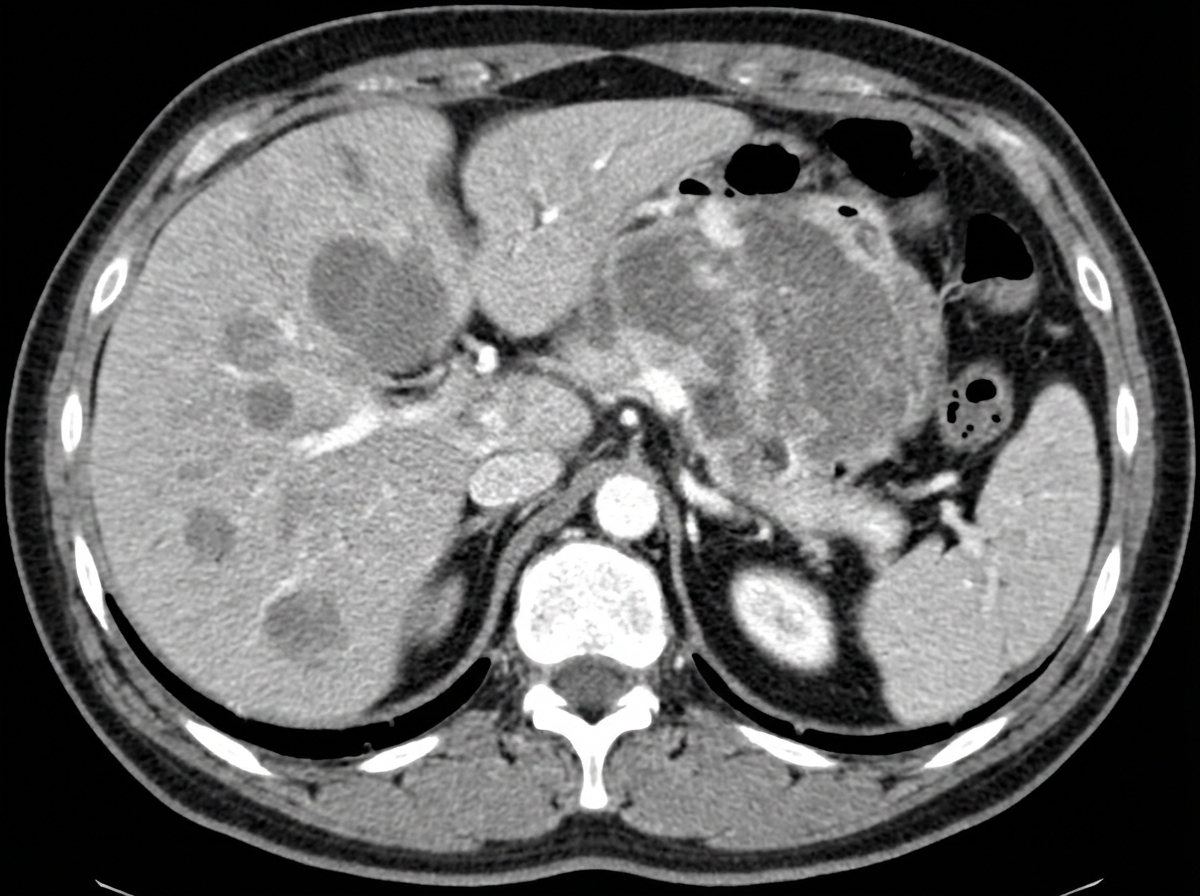

Axial Slice @ T12/L1 - The Celiac Trunk Show

- Landmarks: T12/L1 vertebral body, crus of the diaphragm.

- Great Vessels: Aorta gives rise to the celiac trunk; IVC is to the right.

- Viscera:

- Liver: Right lobe occupies the right upper quadrant.

- Spleen: Lies posterolaterally on the left.

- Stomach: Anterior to the spleen and pancreas.

- Pancreas: Body and neck are located anterior to the aorta.

- Kidneys: Superior poles are visible.

⭐ The celiac trunk is the artery of the foregut, supplying structures from the distal esophagus to the second part of the duodenum.

- At the T12/L1 level, identify the celiac trunk branching from the aorta, just below the diaphragm's crura.